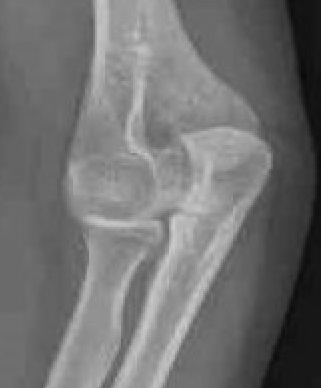

Acute Elbow Dislocation

elbow diselbow dis

Management

1. Reduction under conscious sedation

Traction / countertraction

- use thumbs to correct lateral displacement / push olecranon medially

- flexion to 90o